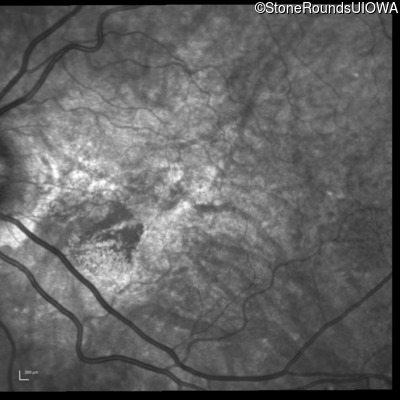

Infrared Fundus Photograph - Right - 20/20 -3 sc

Exemplar